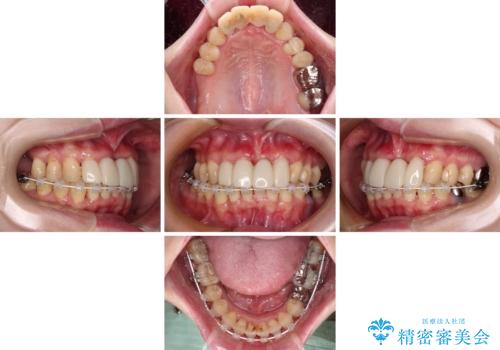

かかりつけ医の治療方針に疑問 歯周病治療と矯正治療を合わせた総合歯科治療

- かかりつけ医にて歯周病治療の名目で治療を行っていたものの、治療プランが明確でないままにインプラント処置を行うとことに疑問を感じ、来院された患者様です。

かかりつけ医では、歯周病治療は終了したため、抜歯を行った右上奥歯にインプラント埋入を行うとの案内があったそうです。

検査を行ったところ、歯周外科処置や抜歯が必要と思われる箇所が散見されたため、あらためて当院に歯周病の初期治療から行うこととしました。

下顎前歯の叢生も気になっており、矯正治療も並行して進めていくこととしました。

自他共に認める、非常に色白の患者様であったため、黄ばんだ歯の色を白くすることを希望されており、歯周病治療の該当部位に限らず、全顎的にオールセラミッククラウンにて補綴治療を行うこととしました。